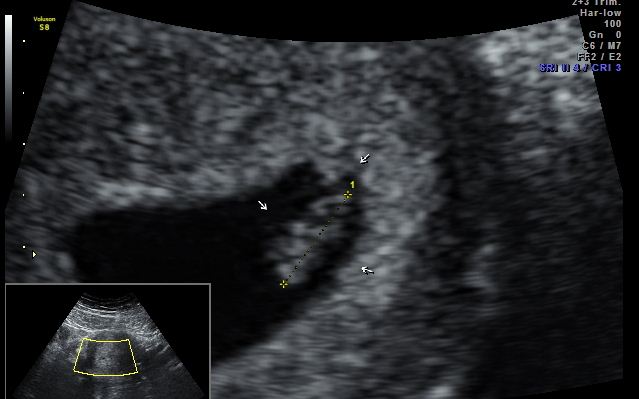

11 weeks down, 29 to go!!!

How big is baby: About the size of a Lime

Gender: Possibly a boy! Just a hunch :)